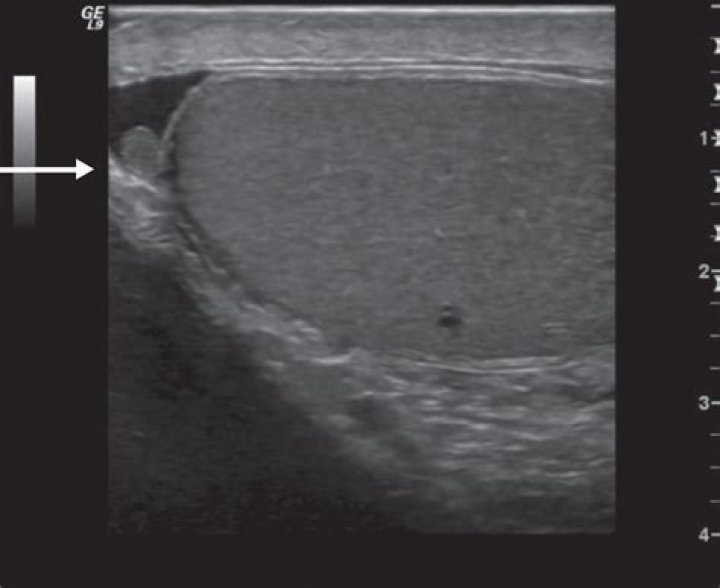

Examination of the Scrotum

The normal testicle is ovoid, smooth, firm, and mildly tender to palpation. The testicle is easily separated from the epididymis, which lies posterior and slightly lateral to the testicle.

What Happens During a Testicular Exam? Your doctor should examine your testicles at least once a year. He or she will grasp one testicle at a time, rolling it gently between the thumb and first finger to feel for lumps. The doctor will also feel if the testicle is hardened or enlarged.

On the back at the top, you should feel the epididymis, a tube that carries sperm. This is a normal lump and may feel tender to the touch. Tell your doctor right away if you notice any swelling, lumps, or changes in the size or color of a testicle.

Gently roll one testicle using the fingers and thumbs of both hands. Feel along the underside of the scrotum to find the epididymis that sits at the back of the testicle. It should feel like a little bunch of tightly curled tubes. Perform TSE on the other testicle.